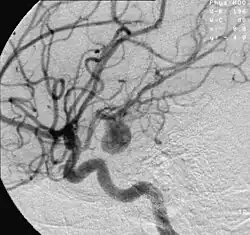

| Angiography of an aneurysm in a brain artery. The aneurysm is the large bulge in the center of the image. | |

An aneurysm is an outward bulging, likened to a bubble or balloon, caused by a localized, abnormal, weak spot on a blood vessel wall.[1] Aneurysms may be a result of a hereditary condition or an acquired disease. Aneurysms can also be a nidus (starting point) for clot formation (thrombosis) and embolization. As an aneurysm increases in size, the risk of rupture increases, which could lead to uncontrolled bleeding.[2] Although they may occur in any blood vessel, particularly lethal examples include aneurysms of the circle of Willis in the brain, aortic aneurysms affecting the thoracic aorta, and abdominal aortic aneurysms. Aneurysms can arise in the heart itself following a heart attack, including both ventricular and atrial septal aneurysms. There are congenital atrial septal aneurysms, a rare heart defect.

Diagnosis of a ruptured cerebral aneurysm is commonly made by finding signs of subarachnoid hemorrhage on a computed tomography (CT) scan. If the CT scan is negative but a ruptured aneurysm is still suspected based on clinical findings, a lumbar puncture can be performed to detect blood in the cerebrospinal fluid. Computed tomography angiography (CTA) is an alternative to traditional angiography and can be performed without the need for arterial catheterization. This test combines a regular CT scan with a contrast dye injected into a vein. Once the dye is injected into a vein, it travels to the cerebral arteries, and images are created using a CT scan. These images show exactly how blood flows into the brain arteries.[39]